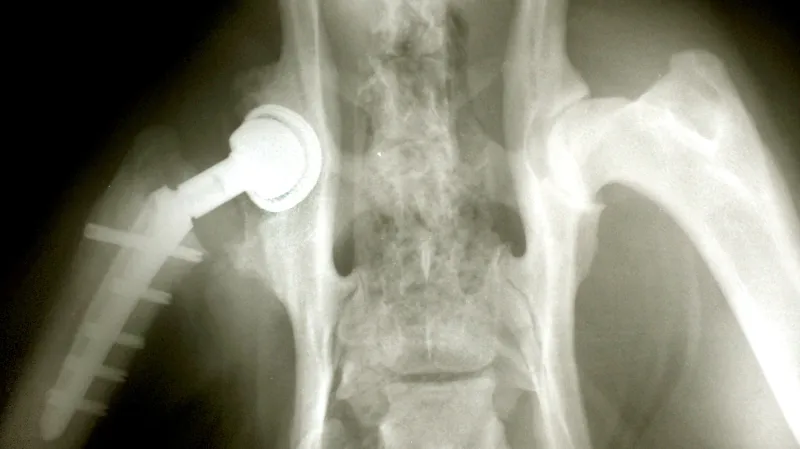

Jako hlavičku kloubu použil Charnley nerezový ocelový balonek, který seděl na dříku vsunutém do stehenní kosti. Pánevní část kloubu pak nahradila vysoce molekulární umělá hmota a dohromady vše spojil takzvaný kostní cement.

Zatímco Brit Charnley použil umělý kloub z nerezu, v současnosti se většina hlaviček vyrábí z kobalt-chromu nebo z keramického materiálu. Časté jsou už i náhrady, které se dají implantovat bez použití cementu. Po roce 2000 se rozšířila také metoda takzvaného Hip resurfacingu, která je vhodná pro dlouhou funkci náhrady.